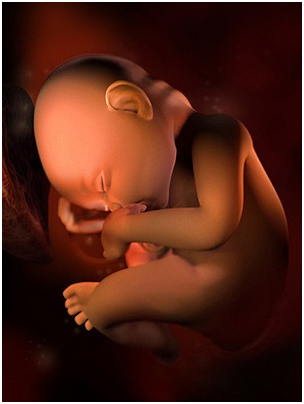

怀孕第16周现在你可以感到胎动啦,可别忘了把你第一次感到胎动的时间记下来哦!一定要抓住这段时...

怀孕第16周现在你可以感到胎动啦,可别忘了把你第一次感到胎动的时间记下来哦!一定要抓住这段时... -

怀孕第17周宝宝能听到你的声音了,尤其喜欢听到妈妈温柔的说话声。所以,现在可是胎教的最佳时期...

怀孕第17周宝宝能听到你的声音了,尤其喜欢听到妈妈温柔的说话声。所以,现在可是胎教的最佳时期... -

怀孕第18周如果你还没有去B超检查,那么最近要去做一次了。胎儿开始有频繁地胎动了,借助听诊器...

怀孕第18周如果你还没有去B超检查,那么最近要去做一次了。胎儿开始有频繁地胎动了,借助听诊器... -

怀孕第19周现在你有必要准备孕妇装了,一身合体的孕妇服会把你的孕期装点得分外精神,你还要坚持...

怀孕第19周现在你有必要准备孕妇装了,一身合体的孕妇服会把你的孕期装点得分外精神,你还要坚持... -

怀孕第20周最近你可能会感到挺舒服的:肚子还不是很大,孕早期常见的各种不适多半也已消失;你和...

怀孕第20周最近你可能会感到挺舒服的:肚子还不是很大,孕早期常见的各种不适多半也已消失;你和... -

怀孕第21周最近你可能会感到挺舒服的:肚子还不是很大,孕早期常见的各种不适多半也已消失;你和...

怀孕第21周最近你可能会感到挺舒服的:肚子还不是很大,孕早期常见的各种不适多半也已消失;你和... -